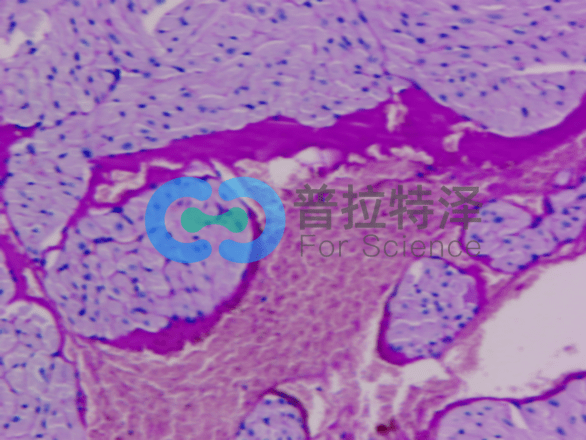

②腎臟疾病診斷

PAS染色在腎臟疾病診斷中同樣發(fā)揮著重要作用。對于腎小球腎炎、腎小管間質(zhì)性腎炎等疾病,PAS染色可以清晰地顯示腎小球基底膜、腎小管及間質(zhì)等結(jié)構(gòu)的變化,有助于醫(yī)生做出準(zhǔn)確的診斷。